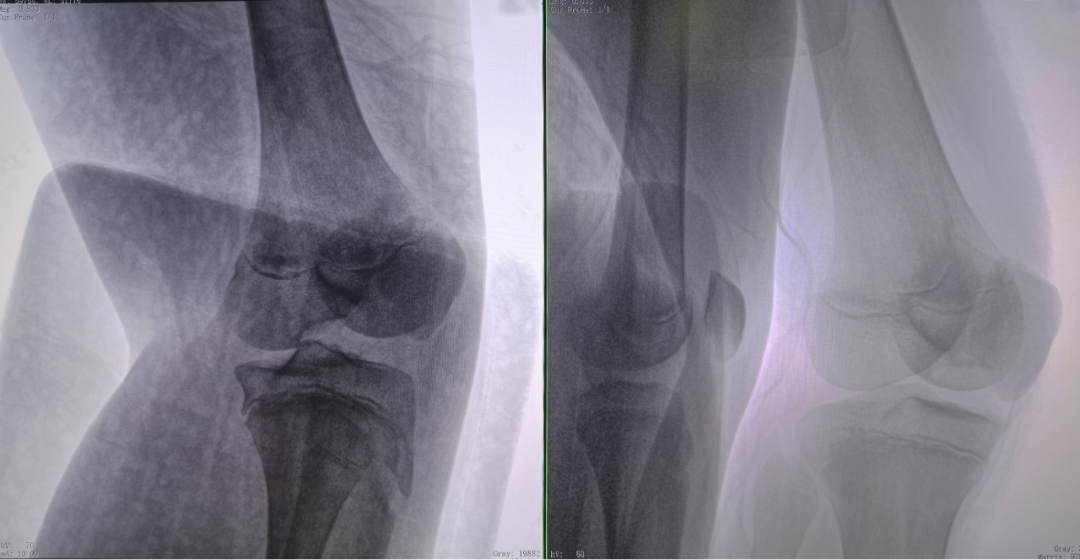

病例1:右侧股骨远端骨骺骨病(13岁)

二维影像看不到病灶点

三维切面影像可以看出病灶点